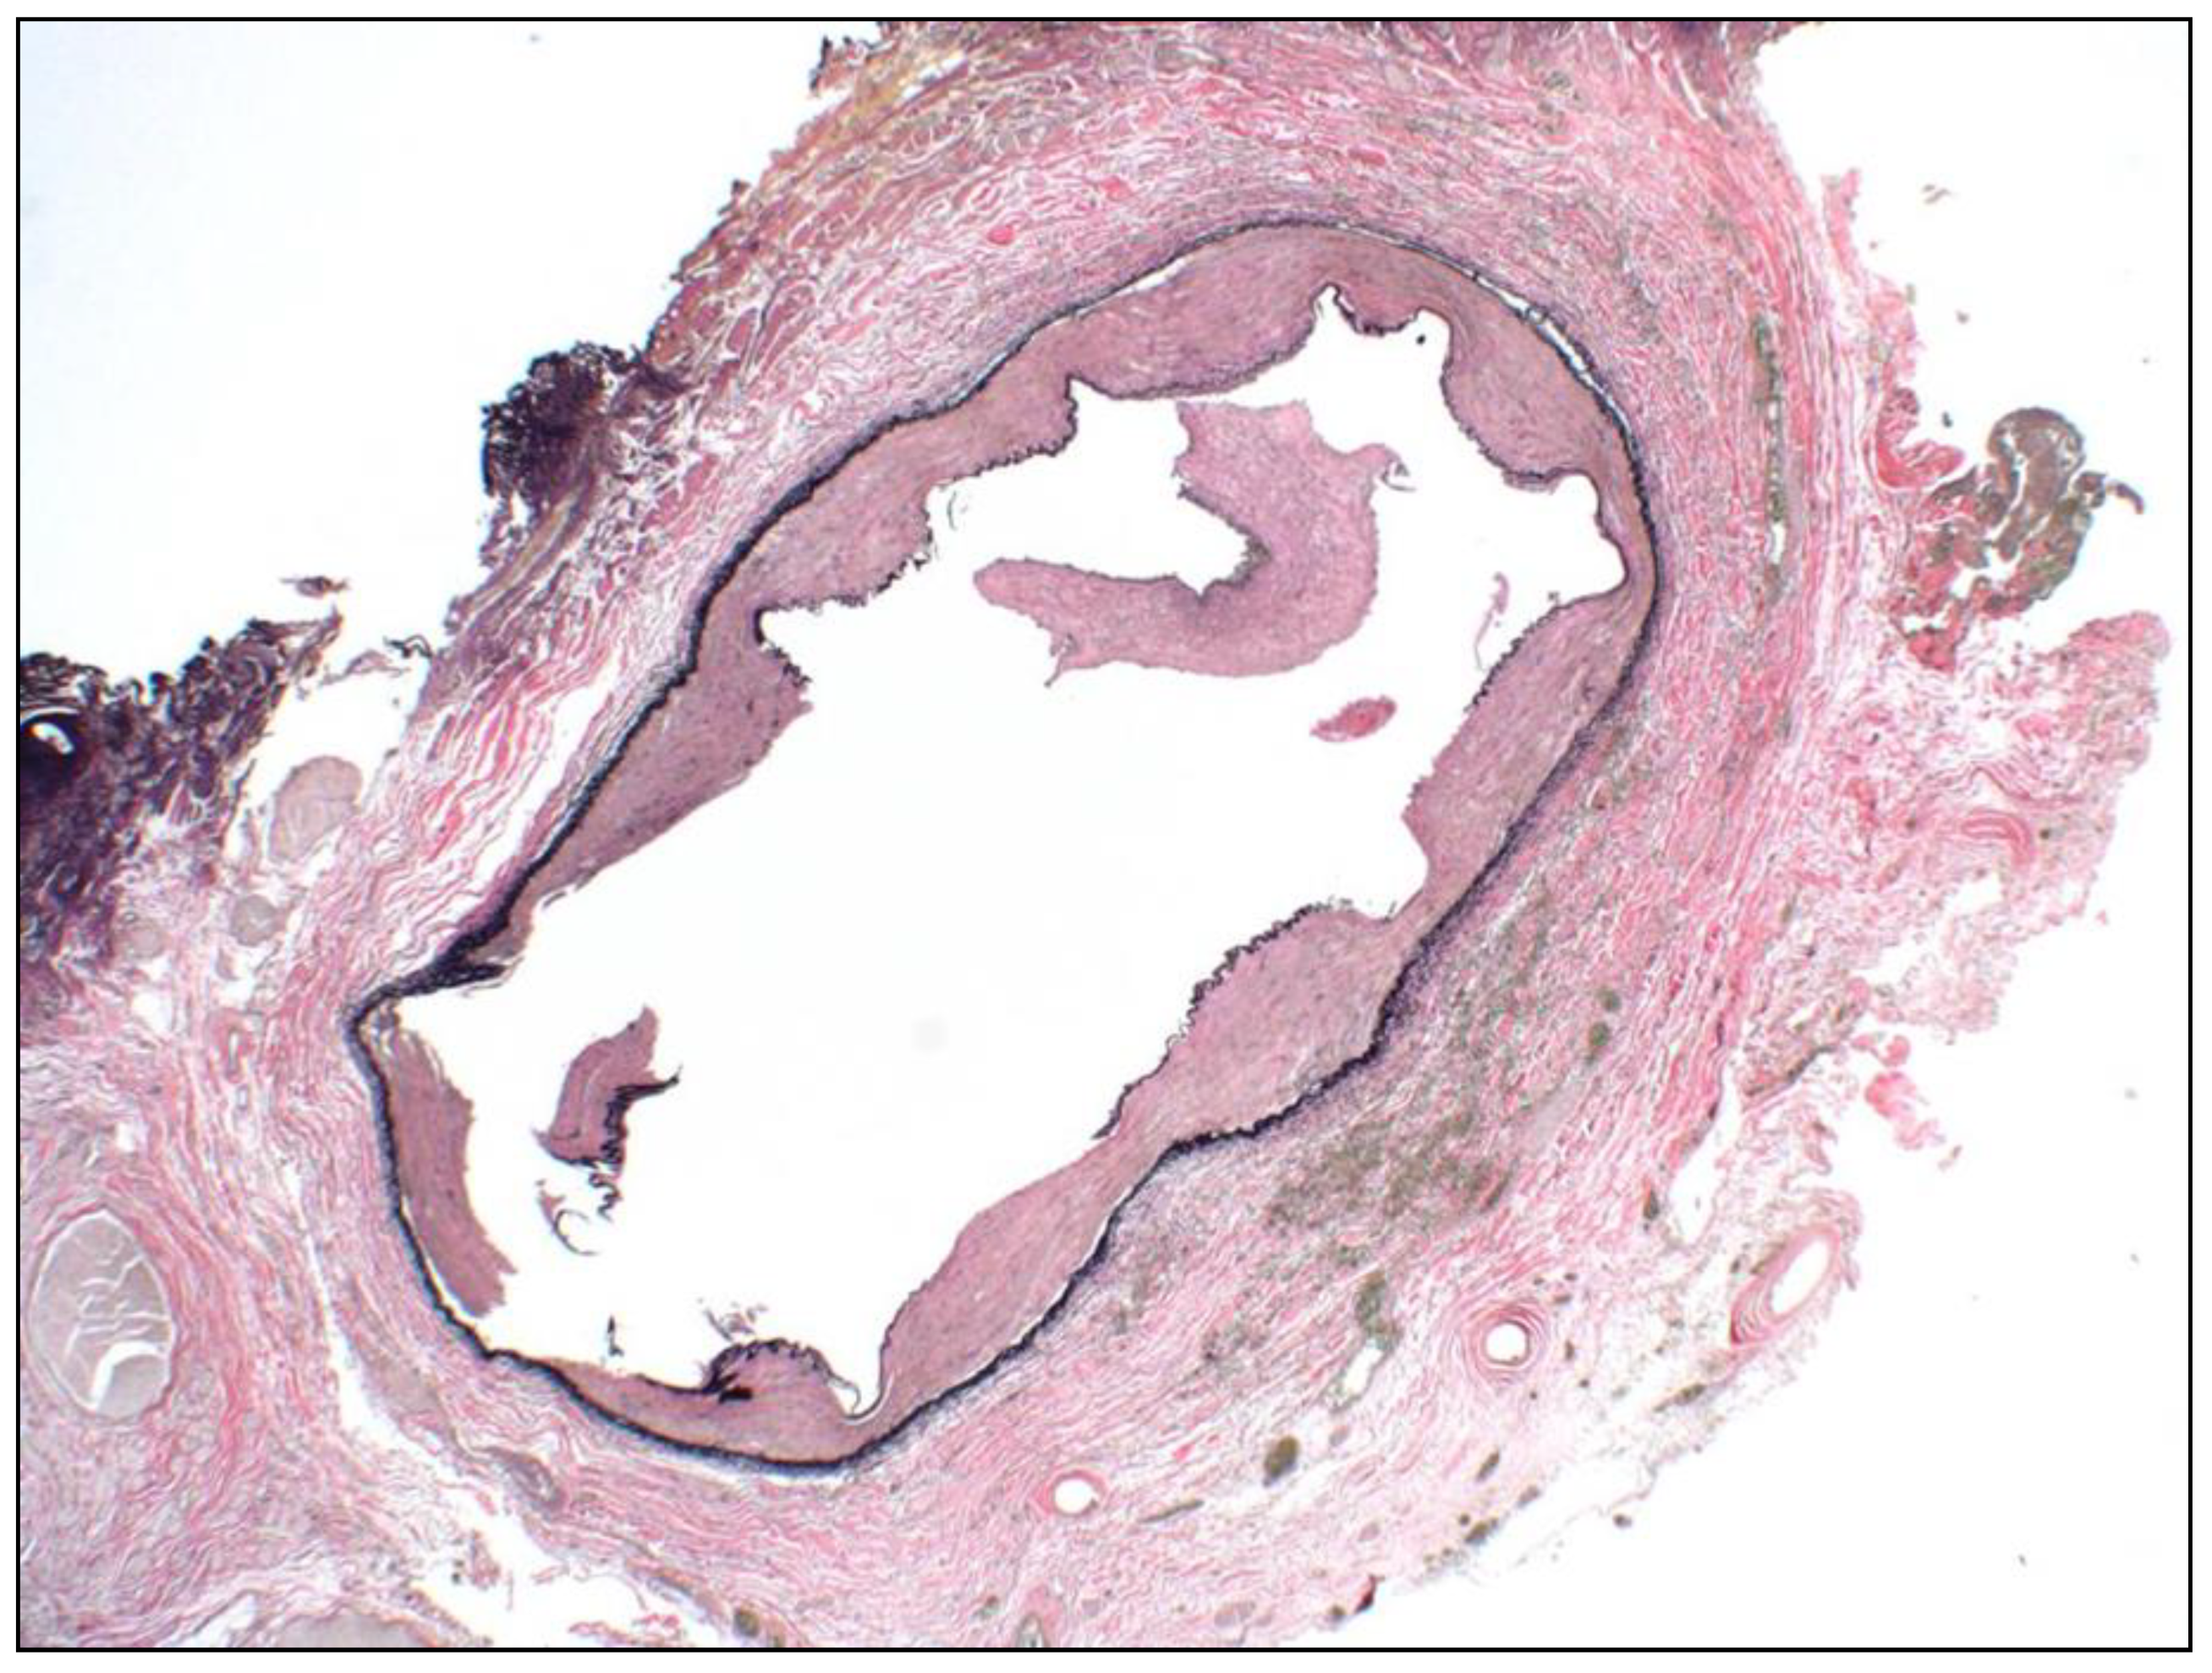

- Bradshaw, S.H.; Kennedy, L.; Dexter, D.F.; Veinot, J.P. A practical method to rapidly dissolve metallic stents. Cardiovasc. Pathol. 2009, 18, 127–133. [Google Scholar] [CrossRef] [PubMed]